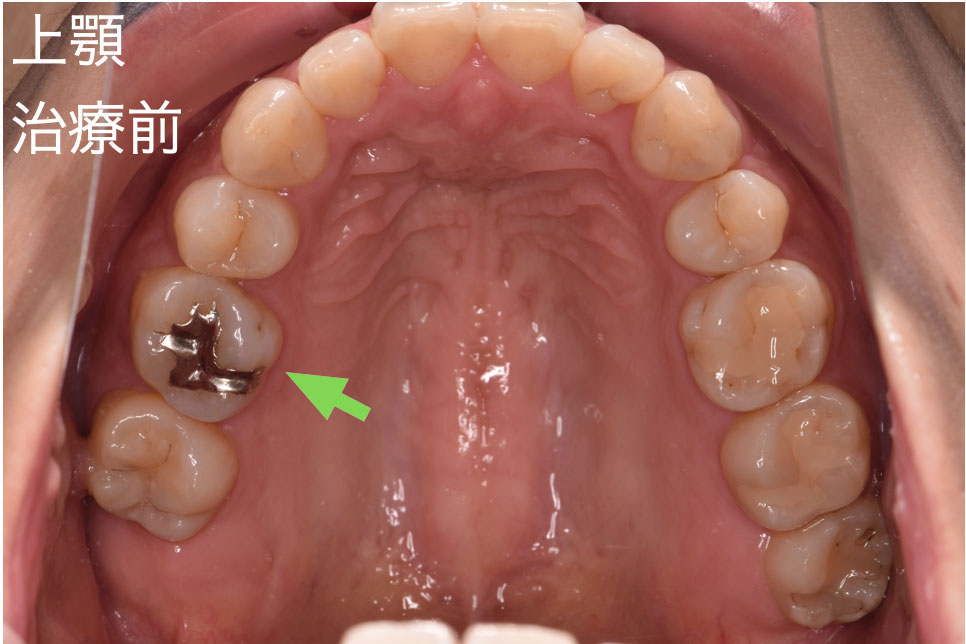

30代女性で銀歯を白い歯にしたいとのことでご来院されました。銀歯で治療されている歯は5箇所ありました。ご本人はいつ治療をしたか覚えていらっしゃらないくらい治療をしてから期間が経過していました。今回は銀歯の範囲に応じて、小さな箇所にダイレクトボンド治療、銀歯の大きな箇所(隣の歯と接している)へはセラミックインレー治療を適用できる判断し、治療を開始しました。

右上第一大臼歯(緑矢印)の咬む面に銀歯があるのがわかります。一見すると異常はないように見えます。